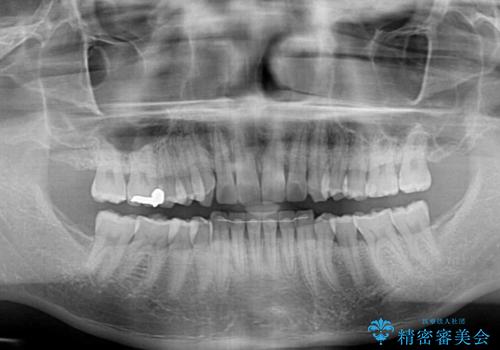

- 前歯のデコボコを気にして来院された患者様です。

当院でインビザライン矯正治療をされている方からのご紹介ということで、インビザラインでの矯正治療をご希望でした。

ワイヤー矯正に比べ来院頻度は低いものの、新幹線での通院のため、やや治療期間が延びることが懸念されました。

配属異動や長時間勤務などによりインビザラインが十分に装着できない期間があり、インビザライン有効期限5年間ギリギリとなってしまいました。